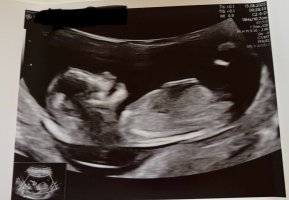

Noen som har lyst å gjette her? 13+2 føler selv jeg ikke ser noe nub, men ifølge både early glimpse og nub theory er det 85% sjans for jente